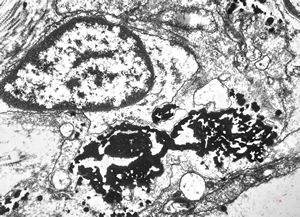

M,43y. | blood - degraded Candida (bone marrow suppression)

M,18y. | blood - clin. susp. leukemia - degraded Candida